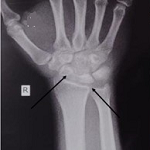

A case of lunatomalacia

Parth Shah

PAMJ-CM. 2022; 9: 38. Published 17 August 2022